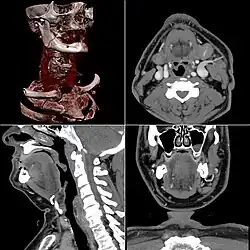

La tomodensitométrie (TDM), dite aussi scanographie, tomographie axiale calculée par ordinateur (TACO), CT-scan (CT : computed tomography), CAT-scan (CAT : computer-assisted tomography), ou simplement scanner ou scanneur pour l'appareil[a], est une technique d'imagerie médicale qui consiste à mesurer l'absorption des rayons X par les tissus puis, par traitement informatique, à numériser et enfin reconstruire des images 2D ou 3D des structures anatomiques. Pour acquérir les données, on emploie la technique d'analyse tomographique ou « par coupes », en soumettant le patient au balayage d'un faisceau de rayons X[1].

Dans les appareils modernes, l'émetteur de rayons X (tube à rayons X) effectue une rotation autour du patient en même temps que les récepteurs situés en face, et qui ont pour fonction de mesurer l'intensité des rayons après qu'ils ont été partiellement absorbés durant leur passage à travers le corps. Les données obtenues sont ensuite traitées par ordinateur, ce qui permet de recomposer des vues en coupes bidimensionnelles puis des vues en trois dimensions des organes. On peut faire ressortir le contraste de certains tissus, en particulier des vaisseaux sanguins, en injectant un produit dit « de contraste » (un complexe de l'iode) qui a la propriété de fortement absorber les rayons X et donc de rendre très visibles les tissus où ce produit est présent (qui apparaissent alors hyperdenses, c'est-à-dire plus « blancs » sur l'image). Grâce aux tomodensitomètres multidétecteurs (ou multi-barrettes) à acquisition spiralée (déplacement lent de la table d'examen durant l'acquisition), on obtient depuis les années 1990 une exploration très précise d'un large volume du corps humain pour un temps d'acquisition de quelques secondes.

Celles-ci se présentent sous la forme de « coupes » ou tranches d'épaisseur millimétrique (de 0,4 mm à 10 mm) que le radiologue peut étudier dans tous les plans de l'espace (sagittal, axial, coronal et obliques), et qu'il s'agit de post-traiter (augmentation de l'épaisseur des coupes visualisées, mise en valeur de certaines densités, reconstructions volumiques en 3D, extraction des vaisseaux ou des structures osseuses, navigation virtuelle endoscopique, etc.).